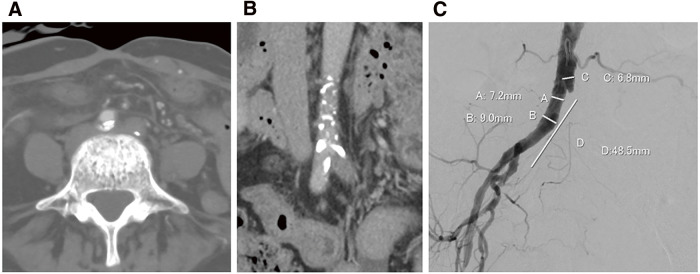

The patient previously underwent surgery for cervical cancer. She reported intermittent claudication, and computed tomography (CT) revealed total occlusion of the left iliac artery. We conducted endovascular treatment (EVT) using balloon-expandable covered stents (BECS). The patient underwent colostomy closure after EVT. The patient reported intermittent claudication beginning the day after the procedure. The CT showed a collapse of the distal side of the stent implanted in the right common iliac artery, accompanied by localized thrombo-occlusion. During open surgery, metal hooks typically affect the iliac artery; force transmission through the tissue may indirectly compress the iliac artery, leading to BECS failure.

患者曾接受过宫颈癌手术。她报告出现间歇性跛行,计算机断层扫描(CT)显示左侧髂动脉完全闭塞。我们使用球囊扩张覆盖支架(BECS)进行了血管内治疗(EVT)。EVT 后,患者接受了结肠造口术。术后第二天,患者出现间歇性跛行。CT 显示,植入右侧髂总动脉的支架远端塌陷,并伴有局部血栓闭塞。在开放手术中,金属钩通常会影响髂动脉;通过组织传递的力可能会间接压迫髂动脉,导致 BECS 失灵。